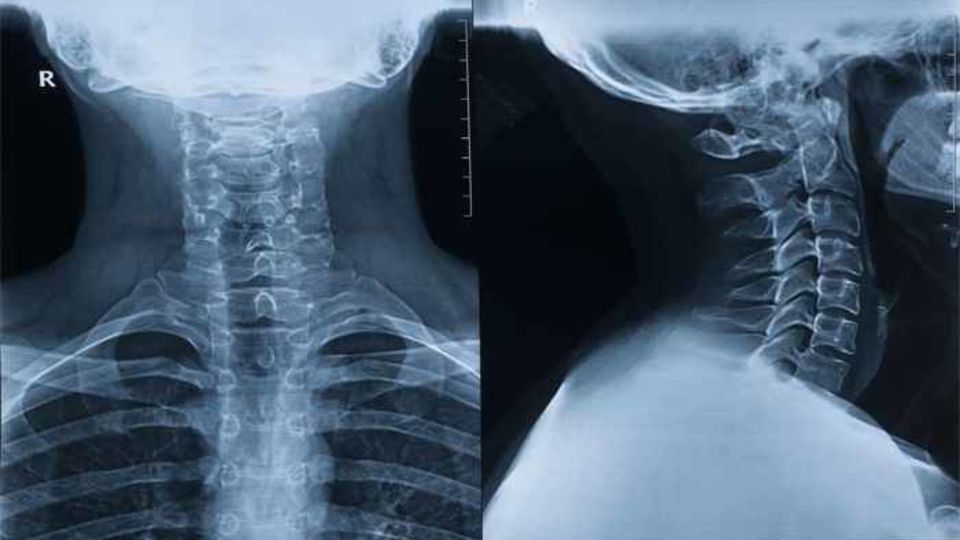

وی افزود: گردن باید همیشه صاف و در امتداد ستون فقرات باشد بنابراین خمکردن گردن برای کار با موبایل یا غذا خوردن و یا نشستنهای غلط میتواند به مرور باعث تخریب مهرهها و حتی نیاز به چندین جراحی شود.

این متخصص جراحی مغز و اعصاب و دیسک و ستون فقرات تصریح کرد: بالش بلند، کفش پاشنهدار یا عادت به نشستن خمیده از جمله عواملی است که گردن و ستون فقرات را دچار آسیب جدی میکند از این رو همه افراد باید یاد بگیرند روی صندلی صاف بنشینند، ارتفاع میز کارشان تا نوک سینه باشد و هنگام کار با موبایل یا مانیتور، دستگاه بالاتر از سطح چشم قرار گیرد تا گردن خم نشود.

ایزدفر گفت:در خواب نیز بالش باید حذف شود و تنها یک حوله لولهشده در زیر گردن قرار گیرد و خوابیدن به شکم برای گردن بسیار مضر است و بهترین حالت خوابیدن به پهلو همراه با بالشتک کوچک بین زانوها است.